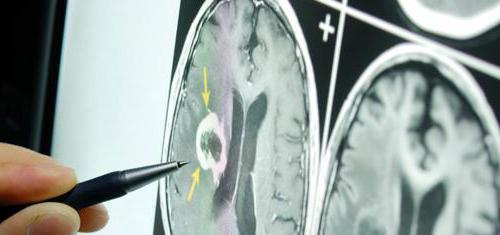

- Опухоли головного мозга.

- локализацию и размеры опухолей, кист, инородных объектов;

Эхоэнцефалография является важным инструментом для выявления образований в головном мозге и определения их точного местоположения. С помощью этой диагностики врачи могут обнаруживать различные заболевания как у детей, так и у взрослых.

Если обнаруживаются значительные отклонения, это может вызвать подозрения у врачей на наличие злокачественных образований. Смещение в диапазоне 4-8 мм является основанием для проведения нейрохирургической операции.